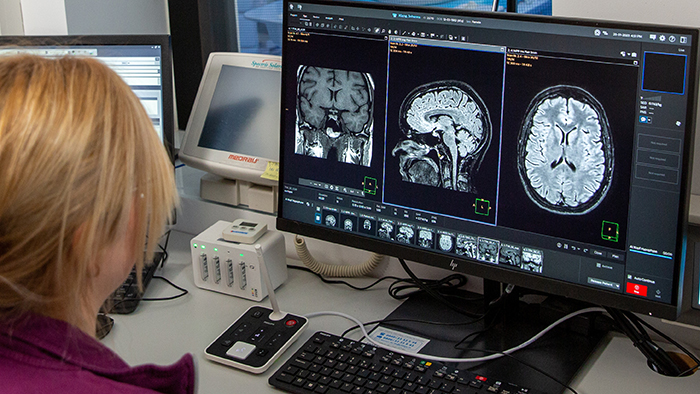

Large screen and easy operation

Philips SmartSpeed is available via MR Workspace, the large-screen operator console that empowers the technologist with integrated AI protocol selection. We also use the new Day manager. During an ongoing examination it allows us to load and adjust the planned examinations for upcoming patients at the same time.”

“The big 27-inch 4K high resolution screen makes a total difference. It shows the large planning images with much higher resolution than we were used to. Anatomic landmarks can be more easily identified, which advances the process. Now it is much easier and faster to plan the new sequences and it’s easier for us to find lesions,” says Dr. Schröter.

“MR Workspace is a tool to operate the system more seamlessly. The user interface is designed in a very advanced way. Operation is intuitive. Many actions can be executed via drag and drop. It is really easy to use and self-explanatory. There are small features and tools that improve the work significantly. For example, being able to copy the geometry of one sequence to the next, without having to make any major adjustments.

Powerful GPU rapidly provides images and reconstruction on large screen

Another important part of MR Workspace is the graphics processing unit (GPU), which allows on-the-fly reconstruction times for images acquired with SmartSpeed. “In addition to seeing razor-sharp images on the large 4K monitor, we also have better and faster reconstruction of the images. Using this extremely high resolution, we sometimes have sequences with up to 800 individual images. The GPU then manages to convert them in a matter of seconds into multiplanar reconstructions. Very impressive.”